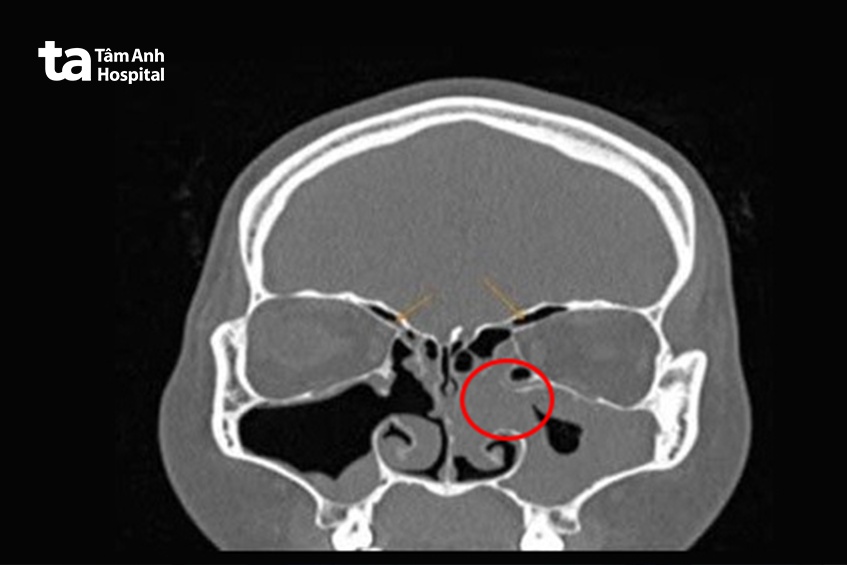

Ngày 14/8, ThS.BS.CKII Trần Thị Thúy Hằng, Trưởng khoa Tai Mũi Họng, Trung tâm Tai Mũi Họng, cho biết kết quả nội soi tai mũi họng bằng máy nội soi Karl Storz cho thấy niêm mạc mũi của chị Hoa phù nề, khe giữa xuất tiết dịch mủ. Bác sĩ nghi ngờ có dị vật ở khe giữa nên chỉ định người bệnh chụp cắt lớp vi tính (CT) hàm mặt. Kết quả ghi nhận rộng lỗ thông xoang hàm, có bọt khí trong xoang, tắc lỗ thông xoang sàng bướm hai bên, tắc ngách mũi trán hai bên. Có tình trạng viêm đa xoang cấp, dày dạng polyp niêm mạc xoang hàm.

Êkip tiến hành mở xoang hàm, sàng, trán, bướm qua nội soi lấy dị vật. Trước tiên, nhỏ thuốc co mạch vào mũi và hút bớt dịch mủ trong hốc mũi. Bác sĩ quan sát hốc mũi bên trái thấy dị vật là miếng gạc (meche) đã mủn, phân rã, mủ lấp đầy khe giữa trái. Bác sĩ lấy ra từng miếng gạc nhỏ rách vụn, dính dịch mủ do ở lâu ngày trong mũi. “Đây là tình trạng gạc bị thấm dịch, nhiễm khuẩn, phân hủy sợi, không còn cấu trúc ban đầu”, bác sĩ Hằng cho biết.